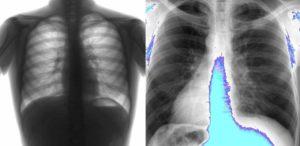

- Спазматический период. В это время клинические проявления достигают максимума. Приступообразный кашель с короткими толчками, идущими один за другим в течение одного выдоха, становится доминирующим. Приступ заканчивается репризом (свистящий звук при резком вдохе), выделением вязкой слизи и рвотными позывами. Вторичные симптомы включают покраснение или синюшность лица, слезоточивость, налитые кровью глаза. В этот период также происходят значительные изменения в легких (см. фото).